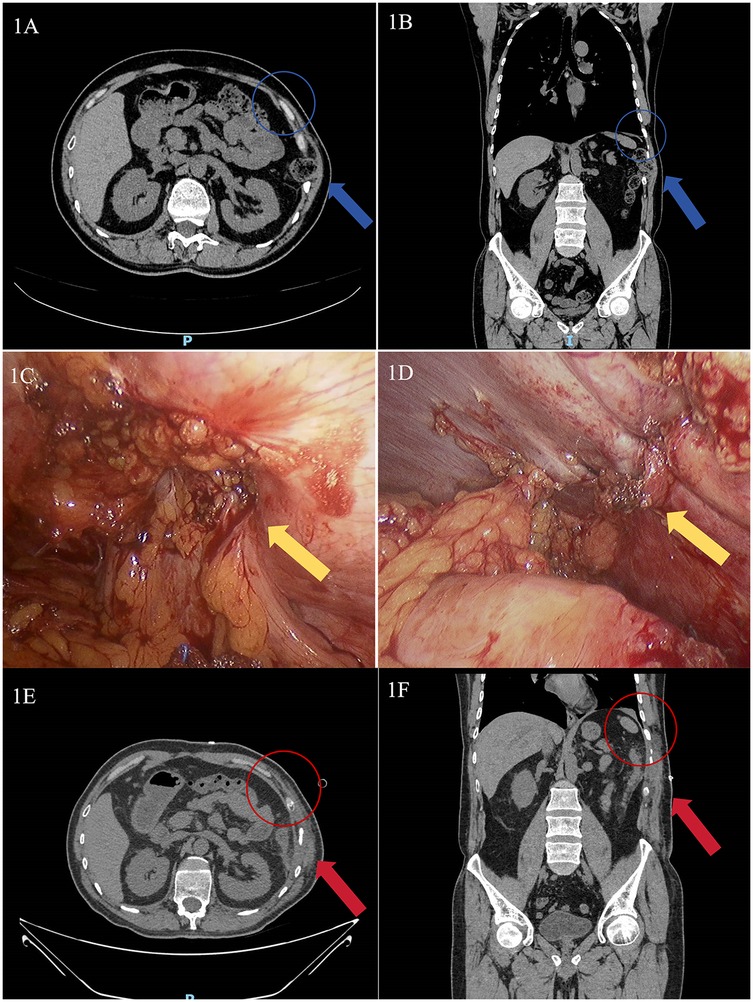

Physical examination revealed a 7 × 8 cm soft, tender mass without fluctuance in the left 10th-11th intercostal spaces along the anterior axillary and midaxillary lines. The skin appeared normal without erythema or ulceration. The mass exhibited mild respiratory movement, with a palpable intercostal weak area showing notable impulse during coughing. Abdominal CT demonstrated a left 10th-11th intercostal abdominal wall hernia (Figures 1A,B).

Figure 1. Abdominal CT and intraoperative images of the patient treated in our hospital. (A) Preoperative axial abdominal CT image (The blue arrow indicates the location of the intercostal hernia, the blue circle demarcates the area of diaphragmatic rupture); (B) Preoperative coronal abdominal CT image (The blue arrow indicates the location of the intercostal hernia, the blue circle demarcates the area of diaphragmatic rupture); (C) Intraoperative view of the hernia sac (The yellow arrow indicates the site of defect, with the colon herniated through it); (D) Intraoperative view after diaphragmatic defect repair (The yellow arrow denotes the post-repair site. The defect was closed with interrupted sutures, and no mesh was deployed); (E) Postoperative axial abdominal CT image (The red arrow indicates the successfully repaired defect with resolution of the hernial sac; the red circle demonstrates the restored continuity of the diaphragm); (F) Postoperative coronal abdominal CT image (The red arrow indicates the successfully repaired defect with resolution of the hernial sac; the red circle demonstrates the restored continuity of the diaphragm).

The diagnosis of transdiaphragmatic intercostal hernia (TDIH) was confirmed, and the patient underwent laparoscopic intercostal hernia repair under general anesthesia. The patient was placed in a supine position. A standard three-port laparoscopic configuration was used. Intraoperative findings revealed a diaphragmatic defect at the left 10th-11th intercostal space with herniation of the descending colon (Figure 1C). The incarcerated colon was reduced, and the diaphragmatic defect was repaired with interrupted 2-0 Prolene sutures (Figure 1D). A synthetic mesh was not used as the defect was deemed repairable under minimal tension. The patient recovered well and was discharged on postoperative day 7. One-month follow-up CT showed no abnormalities (Figures 1E,F), with no recurrence observed during 6 months of follow-up.